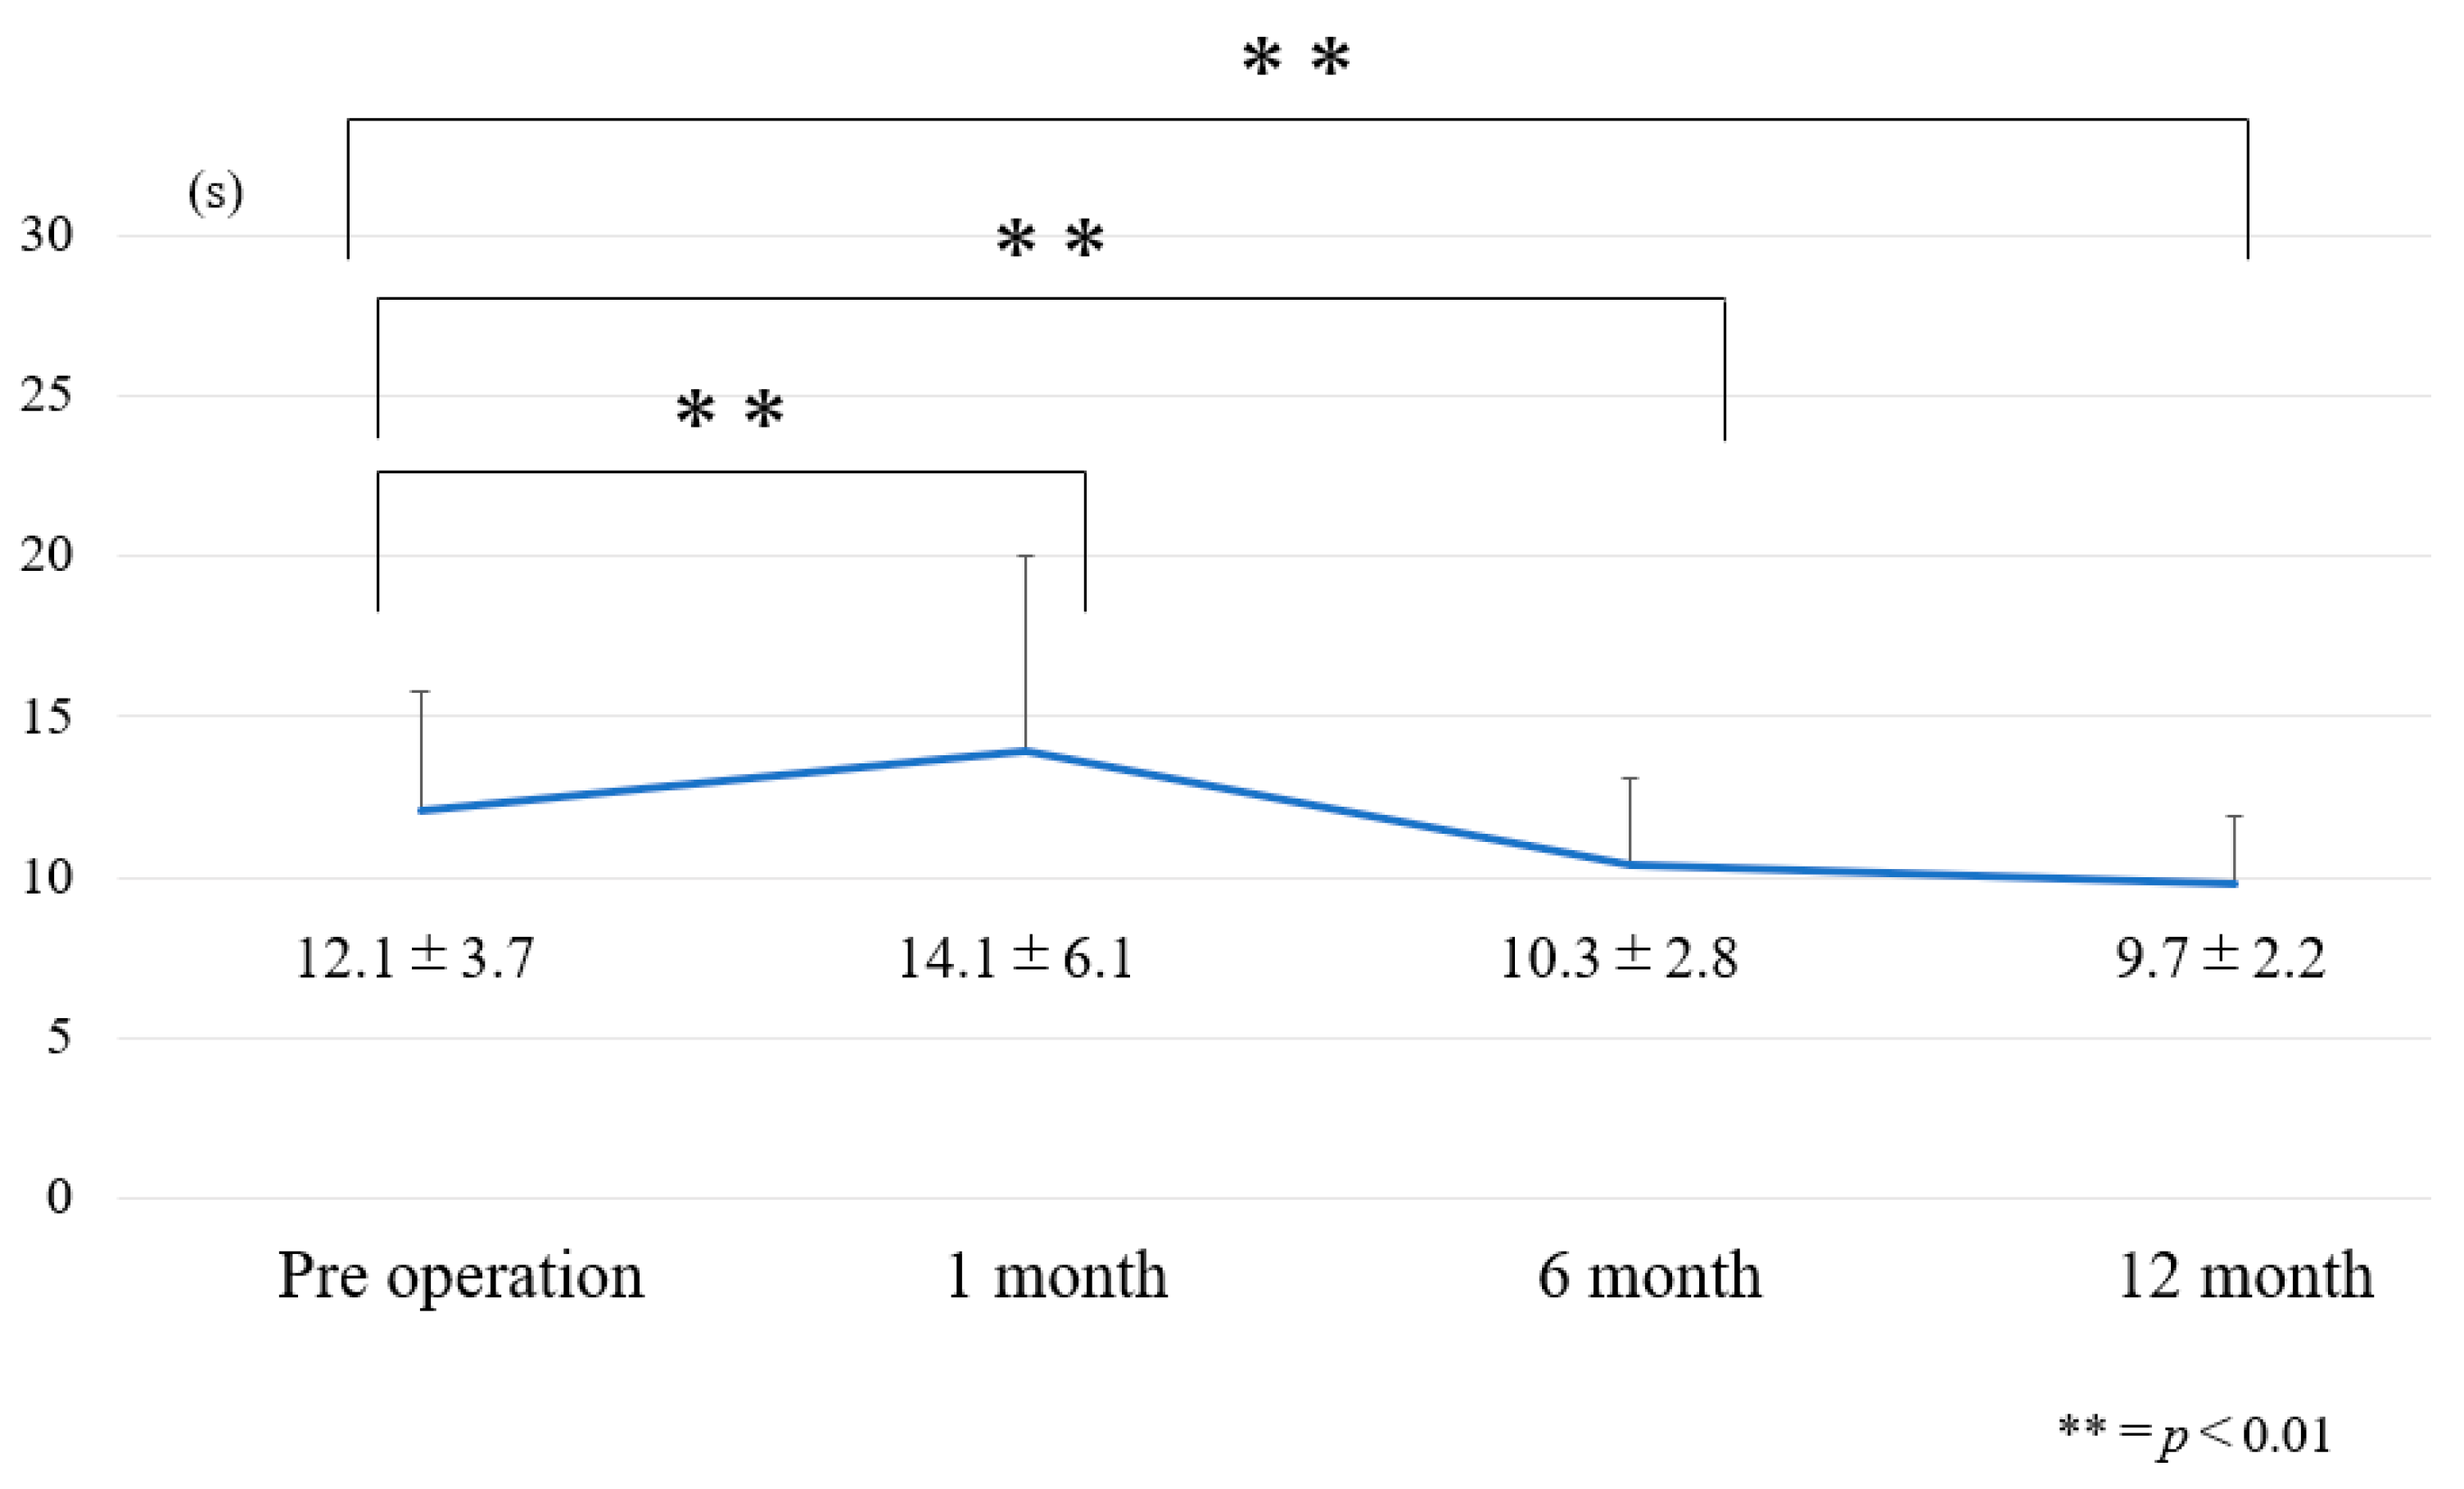

2.2.2. Timed Up-and-Go Test (TUG)

3.1. Chronological Results of 10 m Walk Velocity and TUG (Figure 6 and Figure 7)

3.2. Internal Responsiveness